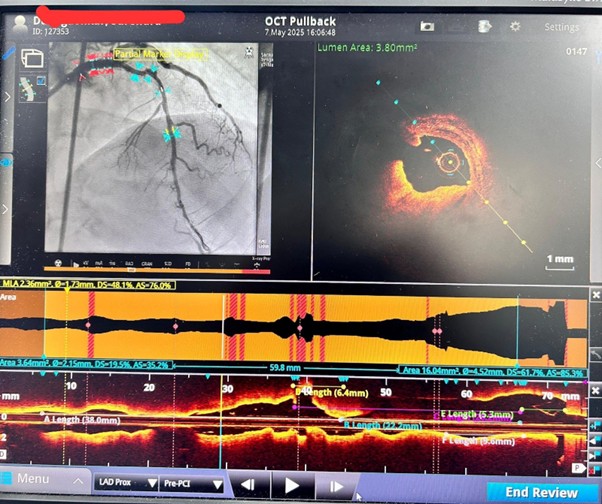

To ensure maximum precision and safety, the procedure was performed using Optical Coherence Tomography (OCT) guidance, an advanced intracoronary imaging technique that allows high-resolution assessment of vessel anatomy, plaque characteristics, and aneurysm morphology. OCT imaging enabled accurate evaluation of the critical blockages and the LAD aneurysm, allowing meticulous procedural planning.